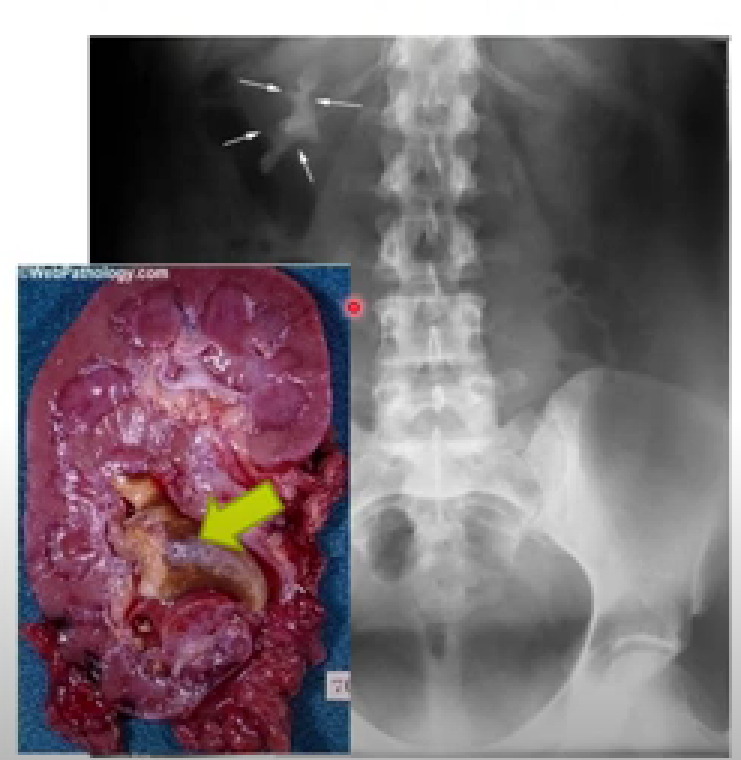

What is staghorn calculi?

Renal calculi in the greater calices and renal pelvis that looks like the horn of a stag.

What are staghorn calculi made of?

Magnesium ammonium phosphate.

What abnormality in the urine causes the formation of staghorn calculi?

Abnormally high pH.

What causes high urine pH that then causes the staghorn calculi?

Proteus mirabilis.